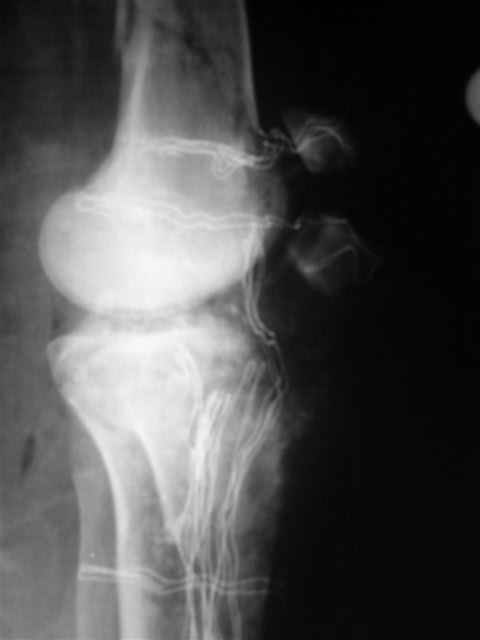

В первом письме я упомянул о закрытом повреждении правого голеностопного сустава, эверсионно-пронационный механизм травмы - перелом внутренней лодыжки( поперечный, на уровне суставной щели) и отрывной перелом бугорка Chaput. После обработки открытых переломов бедра и большеберцовой кости в эту же сессию перелом внутренней лодыжки фиксировал двумя расходящимися спицами, бугорок Chaput двумя тягловыми винтами 3,5 мм. Раны заживают благополучно. Учитывая повреждение наружной группы мышц, активное разгибание в голеностопном суставе ограничено. Пассивная + пассивно-активная мобилизация голеностопного сустава с физиотерапевтом.